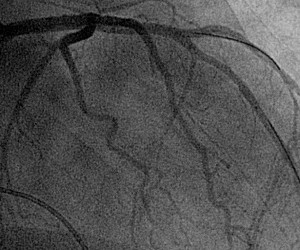

Ученые в процессе использования недавно одобренной систему компьютерной томографии сумели значительно сократить уровень облучения у пациентов, подвергающихся коронарной ангиографии.

«Подвергание облучению в процессе диагностики не может не тревожить», - заметил Маркус Чен, ведущий автор исследования из Национальных институтов здоровья в Вифезде. „Сокращение уровня облучения с сохранением качества диагностического сканирования прекрасно достигается с помощью нового компьютерного томографа второго поколения с 320 датчиками“, - сказал он.

Коронарная ангиография или коронарография — неинвазивное исследование с высокой диагностической точностью. Особенно эффективна и безопасна коронарная ангиография для исключения болезни коронарной артерии у пациентов с острыми болями в груди. Клиническая польза метода ранее была значительно снижена из-за облучения и потенциального развития рака. Новый технологический прогресс позволил существенно обезопасить метод.